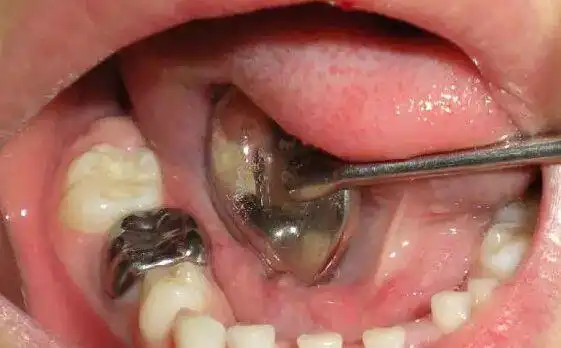

求助,八岁半的小男孩,第一双尖牙烂了,医生说等换牙,可是每天难受怎么

图片尺寸561x348